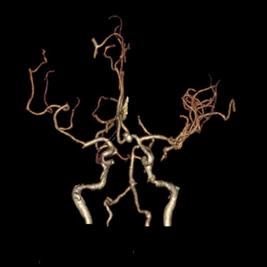

病例3:左侧椎动脉V4段开窗畸形